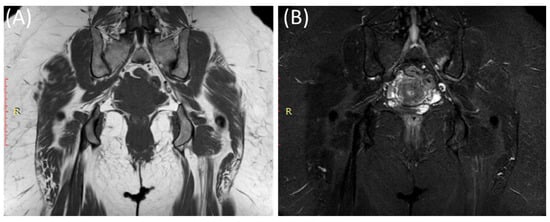

Figure 6.

Coronal T1-WI image (A), coronal T2-WI image (B) and coronal T2-fat suppression image (C) showing sclerosis and mild irregularity in both sacroiliac joints, more on the left side with no evident bone marrow edema in a 52-year-old female with chronic low back and hip pain suggestive of bilateral chronic sacroiliitis.